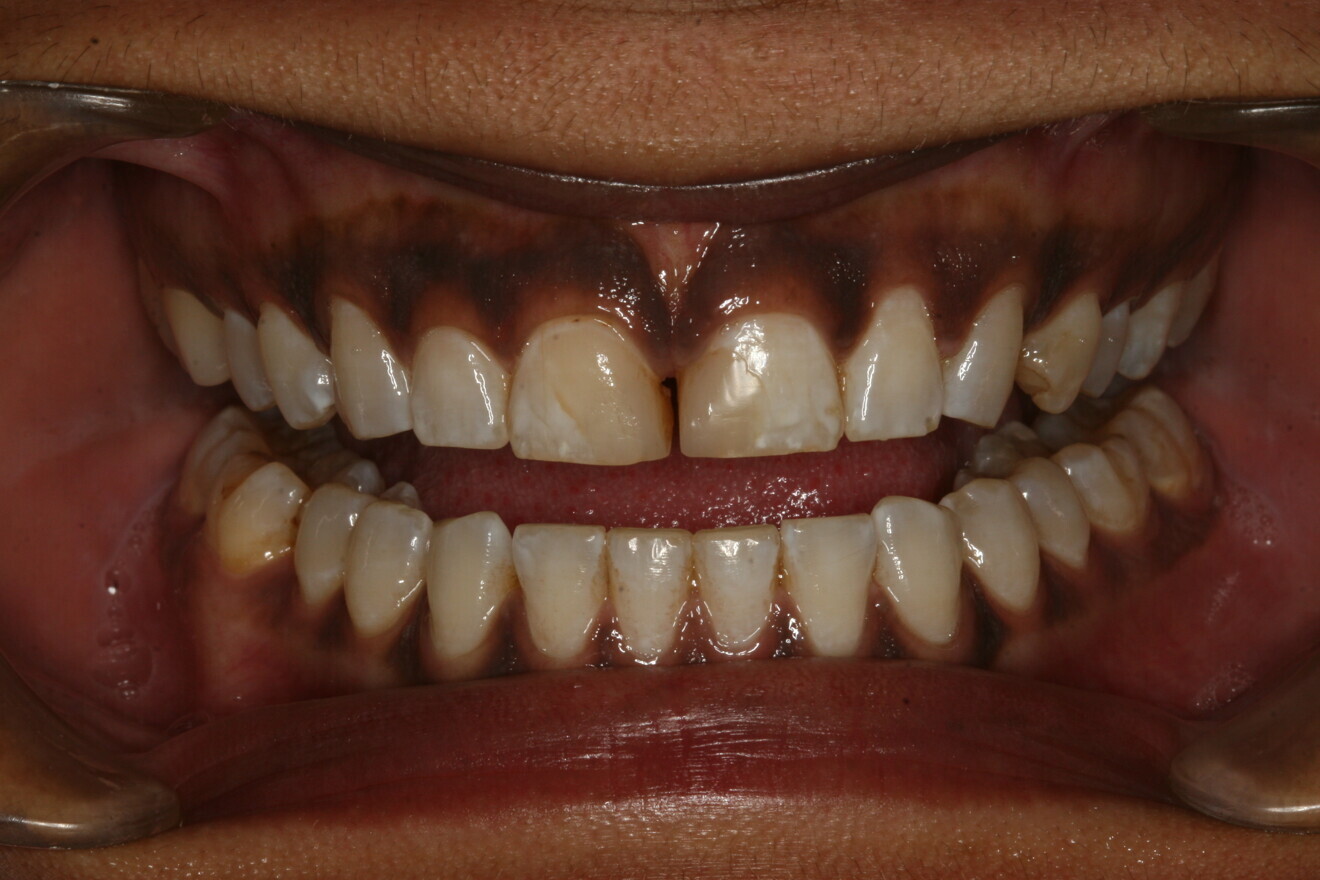

Fig. 9: Post-op retracted view.

The patient returned the following day. Her functional oc­clusion was evaluated, and her teeth were inspected for any re­sidual cement. Postoperative radiographs were taken to con­firm positive seating of the margins and the absence of any residual interproximal cement. Maxillary and mandibular alginate im­pressions were taken along with a polyvinylsiloxane bite reg­istration for fabrication of a maxillary full-arch bite guard for night-time wear.6 Postoperative home care instructions were given, and the patient was scheduled for a follow-up appoint­ment for additional photographic documentation, a final check for function and aesthetic evaluation, and delivery of the bite guard (Figs. 8 & 9).6